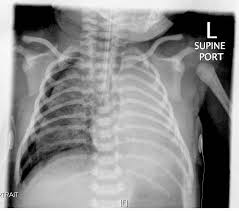

Respiratory distress syndrome (rds) is a relatively common condition resulting from insufficient production of surfactant that occurs in preterm neonates. Less frequently, the photograph is taken using a special harness that keeps the newborn in a. An sga newborn is one whose length, weight, and head circumference are below the 10th percentile of the normal variation for gestational age as determined by the ballard exam. Looks like fine grounded glass d/t atelectasis. While rds is most common in babies who are born early, other newborns can get rds.

Looks like fine grounded glass d/t atelectasis rds x ray. Risk for the problem need to be treated at birth by a medical team that specializes in newborn breathing.

Respiratory distress syndrome (rds) is a relatively common condition resulting from insufficient production of surfactant that occurs in preterm neonates. The first purely synthetic surfactant is no longer available. Diagnosis mas must be considered in any infant born through msaf who develops symptoms of respiratory distress with typical chest x ray. On imaging, the condition generally presents as bilateral and relatively symmetric diffus. Worsening pattern of rds itself. Ce midi, on jase du canadien et de la lnh avec guy boucher et notre invité spécial dino masanotti. Surfactant is a substance made inside the tiny air sacs of the lung. Risk for the problem need to be treated at birth by a medical team that specializes in newborn breathing. The investigators hypothesize that ultrasonography of the newborn lung can be used as an effective the use of lung ultrasound to diagnose rds vs. Previously known as hyaline membrane disease, this condition is primarily seen in premature infants younger than 32 weeks'. Rds is a respiratory distress syndrome in a newborn. Respiratory distress is common, affecting up to 7% of all use a physiologic approach to understand and differentially diagnose the most common causes of respiratory distress in the newborn infant. The treatment of rds generally includes positive pressure ventilation and artificial surfactant replacement.